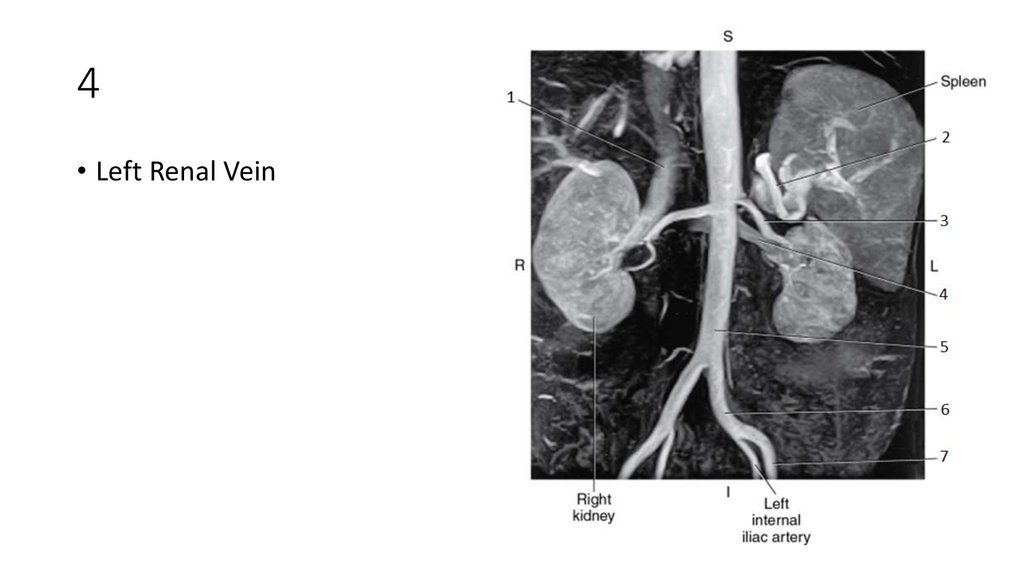

62. 1

63. 1

• Inferior Vena Cava (IVC)

64. 2

65. 2

• Splenic Artery

66. 3

67. 3

• Left Renal Artery

68. 4

69. 4

• Left Renal Vein

70. 5

71. 5

• Aorta

72. 6

73. 6

• Left Common Iliac Artery

74. 7

75. 7

• Left External Iliac Artery